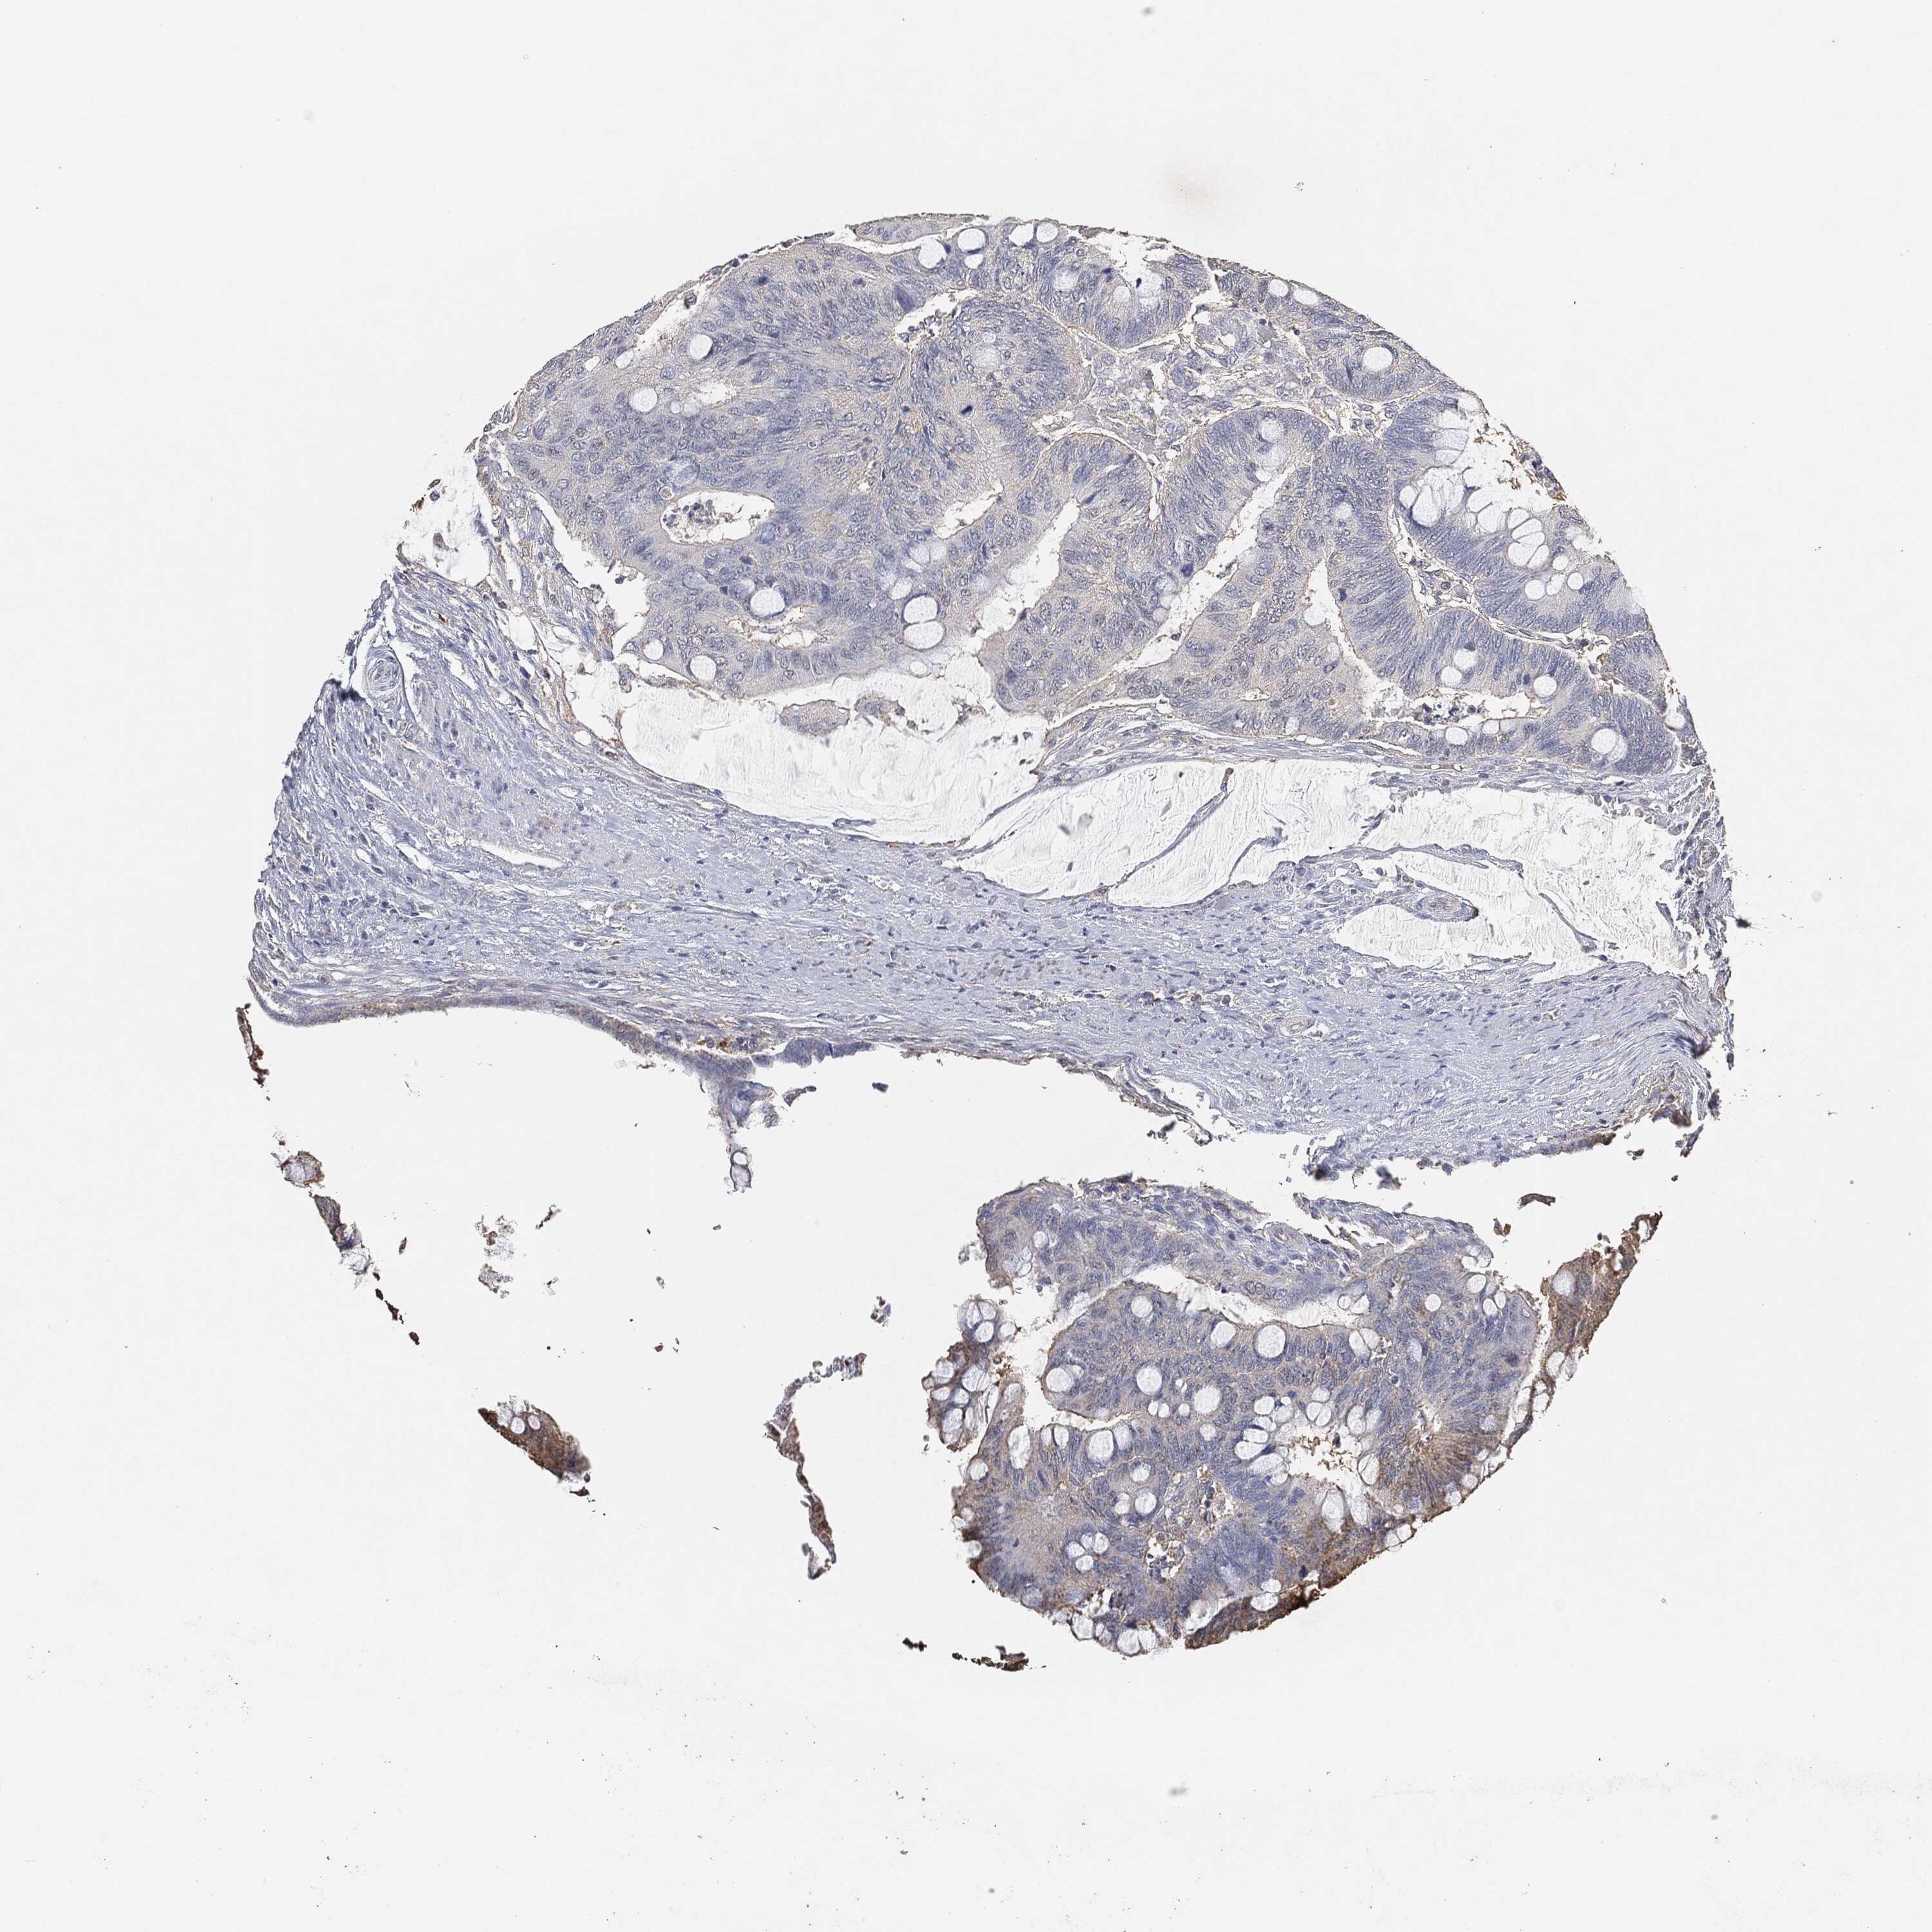

CANCER COLORECTAL CANCER Show tissue menu

Colorectal cancer

Human cancer

Colon adenocarcinoma